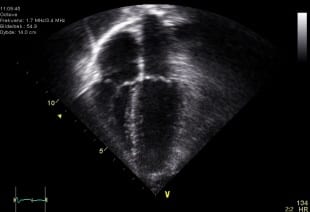

Echocardiography

Echocardiography refers to the use of very high frequency sound waves transmitted through tissue to create static and dynamic (moving) images of the heart and surrounding tissues. By "bouncing" sound waves off of tissue and recording the reflected sounds, images can be made of many structures in the body without using radiation. The term echocardiography, coined in the very early days of sound wave imaging of the body, "stuck" with regard to imaging of the heart to this day, though the use of sound waves to study other parts of the body is now universally referred to as ultrasound. Although developed in the 1970's, the many advances made in this noninvasive technology make it one of the most useful diagnostic tools to obtain immediate and clinically useful information about the heart. Echocardiography can provide a wide variety of information regarding heart function, cardiac valvular anatomy, cardiac chamber sizes and the integrity of the pericardium and great vessels. Aside from images of the heart in motion, measurements of blood flow to and through the heart can give cardiologists a surprising amount of information about the blood flow throughout the rest of the body, and into and through the lungs as well.